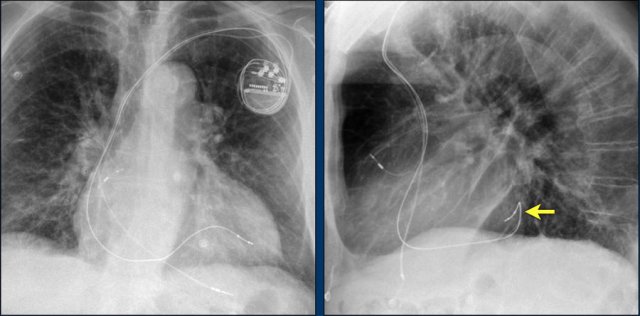

Here a patient with a normally placed ICD on the left image.

Months later there was malfunction due to ICD box and lead rotation (yellow arrow) and retraction (white arrow).

Here another patient with the Twiddler's syndrome.

Notice curling of the lead near the pacemaker and at the tip in the right ventricle (arrows).